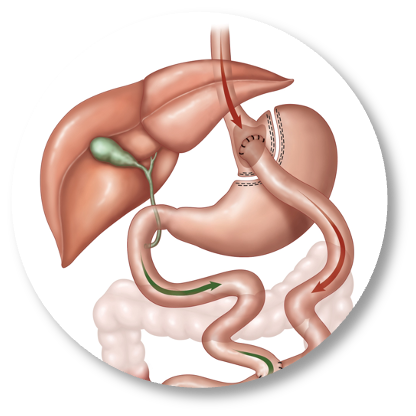

The first cut-free endoscopic treatment for diabesity, ForePass ® is able to replicate the most common types of metabolic surgery (Roux-en-Y Gastric Bypass, RYGB, BilioPancreatic Diversion, and Sleeve Gastrectomy). The first version of our product is aimed at RYGB.

Metabolic Surgery

Only truly effective treatment for diabetes and obesity able to generate 30%+ total body weight loss. Leads to full diabetes, NASH, liver fibrosis, and insulin resistance remission. However, it also leads to 15% complications, including death (0.1-1% with some surgeries).

ForePass ® replicates the three most common metabolic surgeries without requiring a single cut